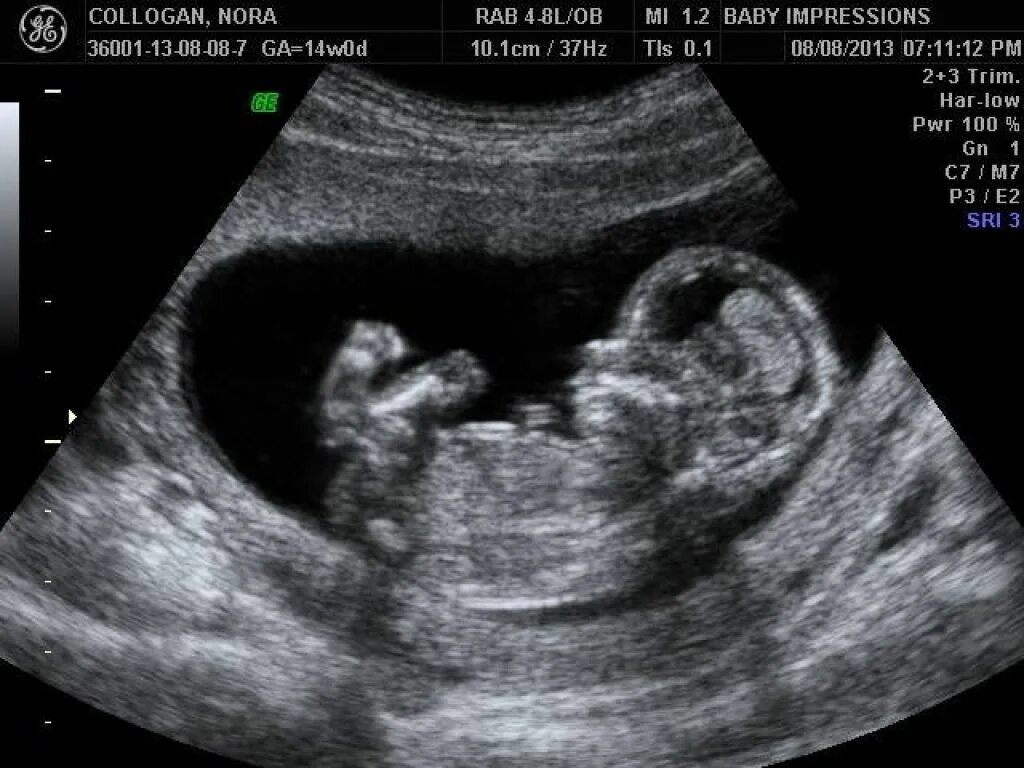

13 недель как выглядит малыш